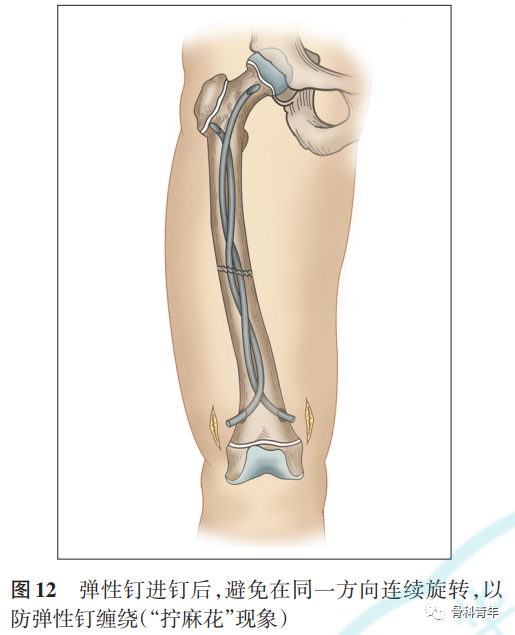

对股骨干和胫骨干骨折,进钉时无论是顺时针或逆时针旋转弹性钉,在打入过程中都要向相反的方向转回同样的角度,避免在同一方向上连续旋转而产生缠绕(“拧麻花”现象)[9-10](图12)。